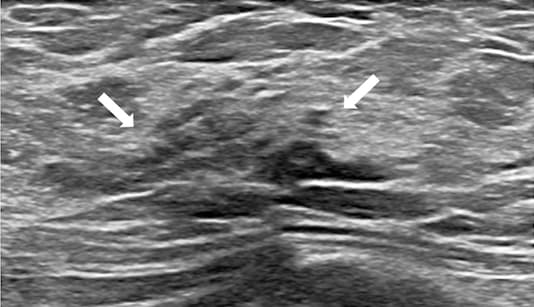

La fraction de densité de proton par IRM est reconnue comme un outil d’évaluation de référence pour quantifier la graisse hépatique. Un travail de recherche publié dans la Revue Radiology évalue la gravité de la stéatose aux moyens de cette pratique. Cet outil IRM est validé par les chercheurs pour...